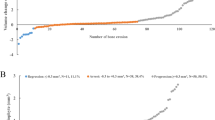

See Table 4 (Additional file 1) for details of the data values and results of the statistical analyses for the longitudinal time main effect analysis, representing the aging effect over 12-months for all participants independent of disease status. In summary, density changes over time included: Cortical bone material density at the MH3 site and UUD trabecular bone apparent density site were significantly reduced over 12-months (MH3 0.6% lower, UUD 2.5% lower). Changes in cortical bone micro-structure over12-months included: UUD cortical thickness and porosity significantly increased over 12-months (Thickness 4.7% greater; Porosity: 29.6% greater). Trabecular bone micro-structure changes over 12-months included: At the UUD site, trabecular number, connectivity and SMI all increased significantly across one year (Number: 1.9% greater, Connectivity 2.7% greater and SMI 3.4% greater). Whereas, trabecular thickness, trabecular spacing and variability were significantly lower (Thickness: 1% lower, Spacing 1.7% lower and variability 1.8% lower). Additionally, at the MH3 site, trabecular bone volume, thickness and thickness variation all increased significantly (volume 0.9% higher, thickness 0.7% higher and thickness variation 1.8% higher).

HR-pQCT imaging - interaction (disease x time) effects

See Table 5 (Additional file 1) for full details of the data values and results of statistical analyses for the RA vs NRA by Baseline vs 12-months (interaction) main effect analyses. There was no significant interaction main effects for any cortical or trabecular bone density or microstructure outcomes examined, which indicates that the rate of change over 12-months was not different for the RA and NRA participants. Or alternately, that the RA participants did not show either an increased or decreased rate of change in bone micro-structure over the 12-months relative to the NRA participants, indicating as well that any underlying difference in bone micro-structure at baseline in the RA participants relative to the NRA participants persisted over the 12-months.